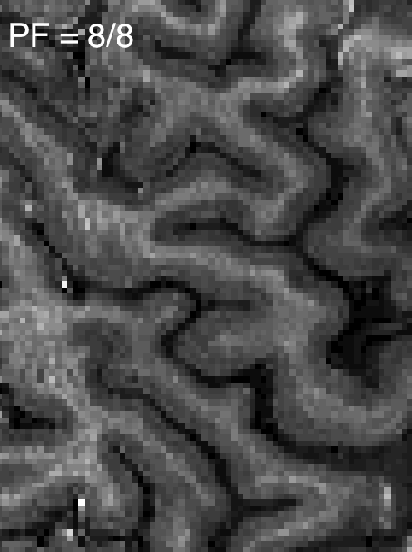

In addition to these theoretical simulations, I tried to investigate the T2*-blurring in-vivo. Two different readout strategies were used to estimate the different T2*-blurring: full k-space acquisition (readout window = 110 ms) and half k-space acquisition (readout window = 60 ms) with the same TE. In order to correct for phase inhomogeneities in the half k-space acquisition, 8% of the k-space lines were acquired symmetrically, across the center of k-space.

The experimental data confirm that full k-space acquisition appears to give better spatial specificity in the phase encoding direction than PF half k-space acquisition (Figs. M/N). Intracortical anatomical layers are blurred in the phase-encoding direction (white arrows), but not in the read direction (black arrows) for the PF half k-space GE-EPI (Fig. M). The discriminability of the intra-cortical layer-dependent signal peaks (Figs. O and P) confirms this (green arrows). Correspondingly, during a finger tapping task, the functional profiles delineated layer-dependent responses with higher effective resolution for the full k-space GE-EPI scheme compared to the case where T2*-attenuation is symmetric in k-space (Figs. Q/R).